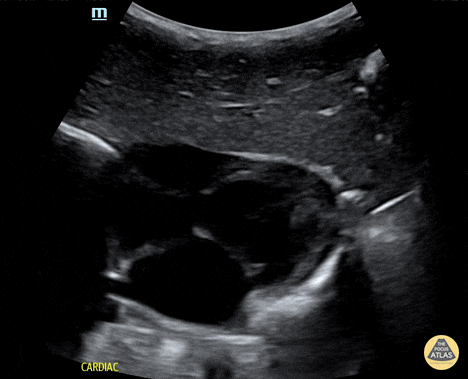

Trauma - Normal subxiphoid evaluation

Normal subxiphoid view on Efast of a 21-month-old patient. Contributor: Jaron Smith, MD, Phoenix Children's Hospital